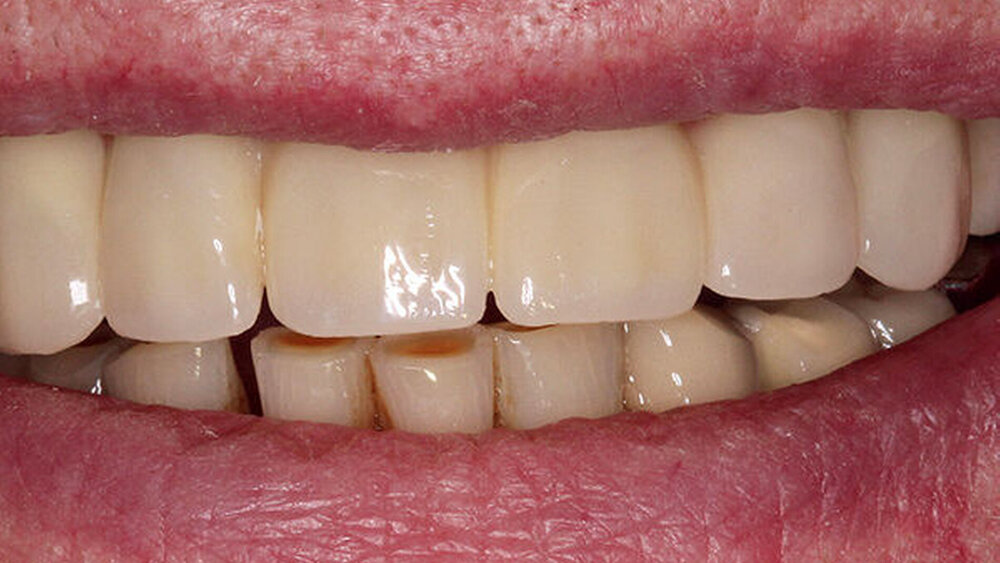

Das ist ein All-on-four- bzw. -six-Konzept für die Sofortversorgung zahnloser Kiefer, korrekt?

Buhtz: Korrekt, die Voraussetzung ist lediglich die Generierung von DICOM- und STL-Daten, die im Computer exakt übereinandergelegt werden können. Dann erfolgen die Behandlungsplanung wie gewohnt mit ICX-Magellan und die provisorische ‧Versorgung mit dem präfabizierten, chairside hergestellten verklebten PMMA-Provisorium (ICX-‧Smile‧bridge). Seit eineinhalb Jahren arbeiten wir zudem mit dem medentis Fräszentrum Denta5 zusammen.

Die ideal prothetisch ausgerichtete Implantatposition ist der wohl wichtigste Erfolgsfaktor in der Implantologie. Mit ICX-Magellan lässt sich das einfach, schnell und kostengünstig realisieren.